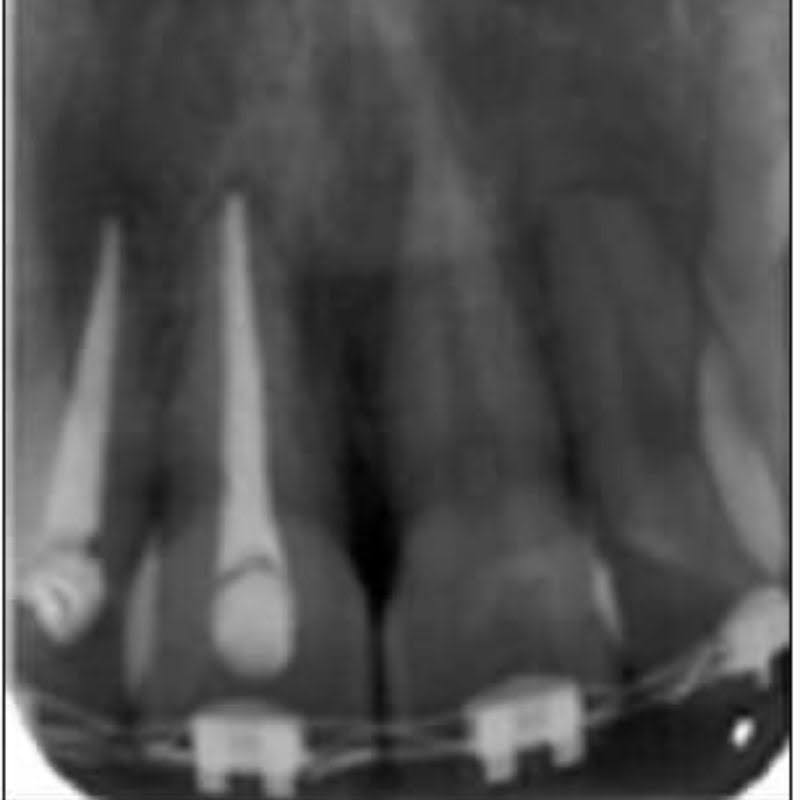

- Que la endodoncia esté bien hecha.

- Que no haya infección en la raíz o el hueso.

Si todo está en orden, el diente se mueve normalmente durante el tratamiento.